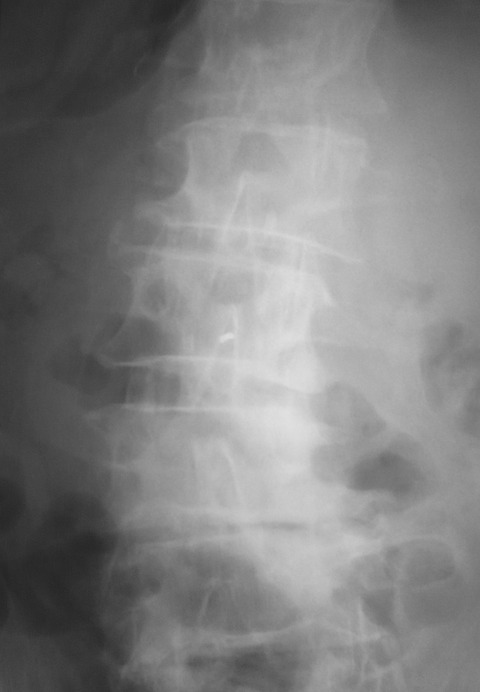

今回の除圧高位はL3/4に高度でしたが、変性側弯を認めました。

ご存知のように変性側弯では腰椎が回旋しているため、正中から掘削することが難しいです。

このような変性側弯症例では正確に正中から進入するため、術前のパイロット刺入の段階で手術台を傾けて腰椎の回旋変位を補正するようにしています。

補正前はこのような状態でした。L3/4の正中がどこか分かりにくいです。これでは正中から進入することが難しいので、イメージを見ながらL3の棘突起が中央にくるように手術台を傾けました。

少し分かりにくいですが、L3の棘突起が中央に位置しています。今回は左側を5度ほど下に傾けることで、このような状態に補正することができました。

このように手術台を傾けて腰椎の回旋の補正をすることで、変性側弯の手術といえども、通常の症例と同様に垂直方向に掘り下げて行くだけになります。

脊椎のエキスパートならこのようなお膳立ては不要かもしれません。しかし一般整形外科医の場合には、このような補正を加えるだけで普段通りの手術に早変わりします。